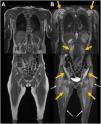

Whole-body magnetic resonance imaging (MRI, Fig. 2) revealed diffuse muscle edema consistent with active DM. Brain MRI (Fig. 3) ruled out central causes and demonstrated an unusual finding of bilateral edema of the masticatory muscles.

Diagnosis and developmentWhole-body MRI revealed diffuse muscle edema consistent with active DM and an unusual finding of bilateral masticatory muscle edema, correlating with chewing and swallowing difficulties. Brain MRI ruled out central causes, confirming that masticatory muscle involvement was the likely cause of symptoms. Despite immunosuppressive therapy, the patient required nasogastric nutritional support.

DiscussionDM primarily affects proximal limb muscles, and MRI findings such as diffuse edema and the “honeycomb” pattern are associated with severe disease, especially in paraneoplastic cases.1,2 However, masticatory muscle edema has not been previously described.3 One hypothesis suggests a selective autoimmune phenomenon affecting highly active muscle groups, while another considers an atypical inflammatory infiltration in paraneoplastic DM.4 The correlation with dysphagia suggests MRI could aid in evaluating refractory symptoms.5 Recognizing this atypical manifestation may influence therapeutic decisions and highlights the importance of detailed imaging in persistent cases. Further studies are needed to determine the prevalence and clinical significance of masticatory muscle involvement in DM. This case expands the spectrum of DM-related muscle involvement and reinforces the role of MRI in detecting atypical patterns (Figs. 1–3).

Whole-body MRI in coronal T1-weighted (A) and STIR-weighted (B) images. Relatively symmetrical, bilateral edema of the proximal musculature (orange arrows), primarily in the scapular and pelvic regions, as well as in the paraspinal muscles. No significant atrophy was identified. Minimal subcutaneous stranding was also noted (white arrows).